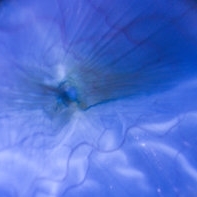

Serous Retinal Detachment and Retinal Infiltrate due to B. Hensele, Cat-Scratch Disease

Serous Retinal Detachment and Retinal Infiltrate due to B. Hensele, Cat-Scratch Disease

Dec 19 2020 by John S. King, MD

64-year-old female had at least a two week history of blurry vision in the right eye. She was being followed for a CRVO in the right eye, and as vision worsened, was referred to our clinic, and saw Dr. Zocchi. Vision in the right eye was CF; there was 1+ cell in the A/C; 1+ vitreous cell was present; disc edema with surrounding SRF as well as a small, white, retinal infiltrate just superior to the optic disc; vessel tortuosity was present as well as a few IRHs (left eye was u/r). There was sub-foveal and PP SRF on OCT. FA in the early to mid phase showed optic disc hyperfluorescence and early filling into the subretinal space. In the later frames there was disc leakage, staining/leakage of the retinal infiltrate, and filling into the subretinal space (See Image). Multiple tests were done, she was started on doxycycline 100 mg BID, and Bartonella serology test came back positive. One week later vision improved to 20/100, a/c cell present, disc edema improved and the SRF was resolving. (will add more photos next visit)

Photographer: Shelly Blair

Imaging device: Optos CA

Condition/keywords: cat scratch retinitis